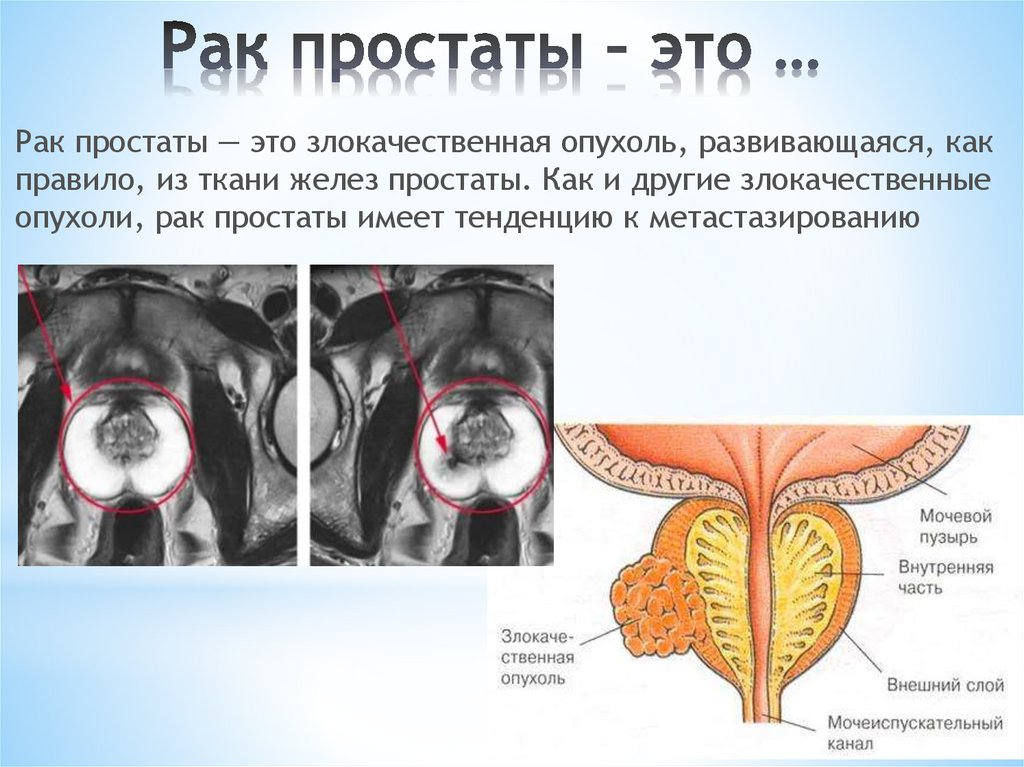

УВТ предстательной железы. Кальцинат предстательной железы. Cancer предстательной железы Предстательная железа MRT. Мультипараметрическое мрт предстательной железы. Предстательная железа кт норма. Аденома предстательной железы мрт

Предстательная железа MRT. Мультипараметрическое мрт предстательной железы. Предстательная железа кт норма. Аденома предстательной железы мрт Гистосканнинг предстательной железы. Трансректальная биопсия предстательной железы под контролем УЗИ. Ангиография предстательной железы. Лимфоузлы в предстательной железе

Злокачественное Перерождение предстательной железы Гистологическая классификация опухолей предстательной железы. Простатическая интраэпителиальная неоплазия. Опухоли предстательной железы факторы. Предраковые заболевания предстательной железы

Гистологическая классификация опухолей предстательной железы. Простатическая интраэпителиальная неоплазия. Опухоли предстательной железы факторы. Предраковые заболевания предстательной железы Злокачественное новообразование предстательной железы. Метастазы предстательной железы. Карцинома предстательной железы. Злокачественные новообразования простаты

Анатомия аденомы предстательной железы. Эктопия предстательной железы. Злокачественная опухоль предстательной железы. Злокачественная аденома предстательной железы

Анатомия аденомы предстательной железы. Эктопия предстательной железы. Злокачественная опухоль предстательной железы. Злокачественная аденома предстательной железы Карцинома 4 степени предстательной железы. Онкология предстательной железы. Опухоль предстательной железы стадии